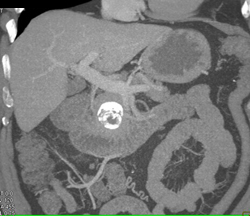

Occlusion of Splenic Vein By Pancreatic Cancer